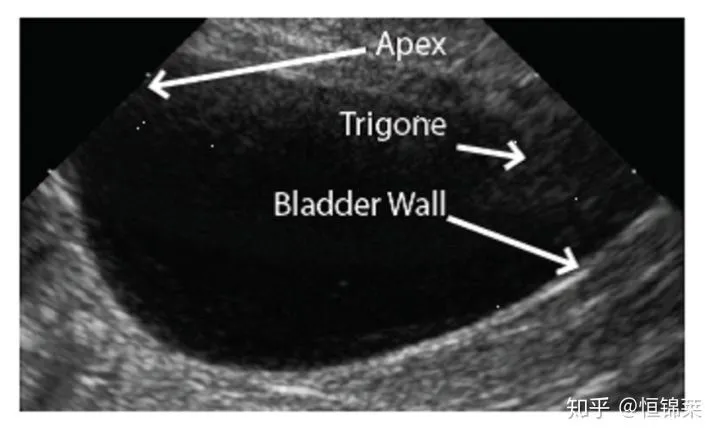

3. Βρίσκεται ακριβώς κοντά στη μέση γραμμή της ουράς κοιλίας κοντά στη λεκάνη, μπορεί να ληφθεί η όψη της μέσης γραμμής της κύστης ή της χοληδόχου κύστης (CC). Σκοπός είναι η αναγνώριση της ουροδόχου κύστης, ιδιαίτερα της κορυφής και της γύρω περιοχής.

Μέση γραμμή της κύστης ή όψη χοληδόχου κύστης σε ημισέληνο: Διαμήκης όψη της υπερηχογραφικής εικόνας της κύστης. Σημειώστε ότι η κύστη είναι γεμάτη με το μεγαλύτερο μέρος της εικόνας. Προσαρμόστε τη ρύθμιση βάθους στο μηχάνημα έτσι ώστε η κύστη να γεμίζει ολόκληρη την οθόνη. Βεβαιωθείτε ότι μπορείτε να αναγνωρίσετε την κορυφή και το τρίγωνο της κύστης και να διακρίνετε το κόλον από το πίσω τοίχωμα της κύστης.